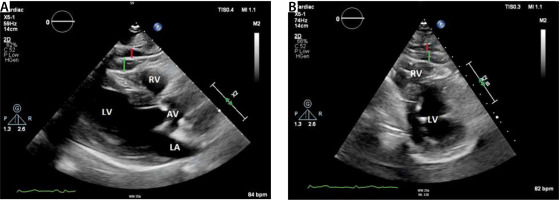

Echocardiography

EAT presents as the hyperechoic area between the ventricular wall and the parietal pericardium [93] (Figure 4). EAT is visually more prominent around the right ventricular free wall. EAT echocardiographic thickness is measured perpendicularly to the myocardial wall in the parasternal long axis, the short axis, and apical long-axis views [94]. A threshold value of 5 mm for EAT thickness has been proposed to identify individuals at higher cardiovascular risk [95].

FIGURE 4

Panel a shows a parasternal long axis view. Epicardial adipose tissue presents as hyperechogenic area between the pericardium (white arrow) and the myocardium. Panel B shows a parasternal short axis view. EAT is best detected at the right atrial free wall. The green line represents EAT thickness measurements. Red line indicates pericardial fat

The advantages of echocardiography are its wide availability, relative cheapness, and no patient radiation exposure. The limitations of echocardiography assessed EAT are the inability of two-dimensional echocardiography to provide accurate volumetric EAT measurements and its high operator-dependency [96, 97]. Some authors have emphasised that EAT can be confused with pericardial effusion [97].